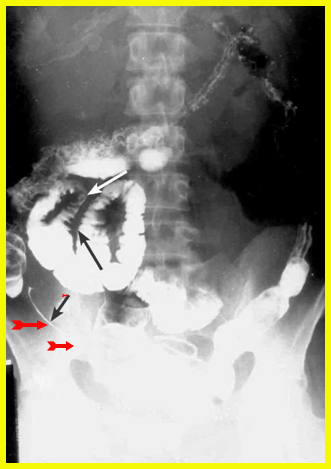

האבחון הרנטגני הוא חשוב. צילום בליעת בריום, אנטרוקליזיס וטומוגרפיה ממוחשבת של הבטן עם בליעת חומר ניגוד הם הכלים העיקריים לאבחנה. קשת של סימנים מצביעה על פתולוגיה במעי הדק.

- הסימן האופייני הוא ה-String sign, המבטא התעבות של דופן המעי והיצרויות של נהור המעי (תצלום 14.4).

- הדופן מעובה, ולכן המרחק בין הלולאות הוא רב (תצלום 15.5).

- הרירית מאבדת את המבנה הרגיל שלה ואפשר לזהות בה פיסורות, תבנית אבני מרצפת, חריגויות ואי-סימטריה (תצלום -17.4 ו-18.4).

- נצורים אפשר להדגים בחלק מהמקרים (תצלום 19.4)

- Skip lesions הם סימן אבחנתי חשוב ביותר, שכן הם מבטאים קטעים נגועים יחידים לאורך כל המעי, ובכל קטע כזה נמצא את המאפיינים הרנטגניים של מחלת קרוהן